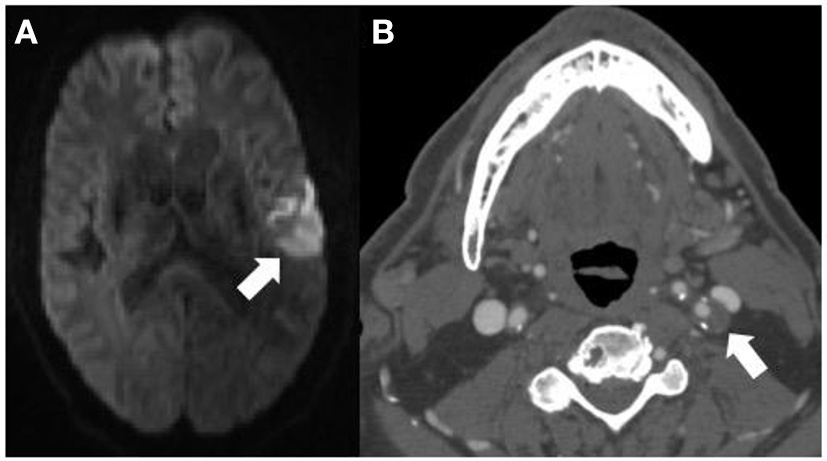

FIGURE 2

www.frontiersin.org

Figure 2. This 71-years-old patient presenting with an acute left middle cerebral artery territory infarction [arrow (A)] did not have any significant stenosis by North American Symptomatic Carotid Endarterectomy Trial criteria on CT angiography (CTA) and was thought to have an embolic stroke of undetermined source. The CTA (B) does however show a large, predominantly non–calcified plaque up to 5 mm in thickness in the proximal left internal carotid artery [(B) arrow] compatible with a vulnerable plaque, potentially the embolic source of the infarction.